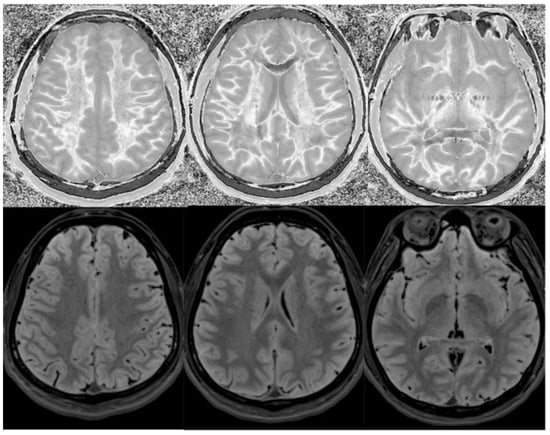

In another example, a matched pair of scans in two teenage boys with impact-related head injury in the same rugby match showed widespread white matter changes in the symptomatic player but not in the asymptomatic one (Figure 17).

Figure 17.

Two boys with mild head trauma. Top row: Narrow middle domain divided Subtracted Inversion Recovery (dSIR) images at the level of the centrum semiovale (left), corona radiata (middle), and basal ganglia (right) in two young men experiencing mild head trauma in the same rugby match. TIshort = 350 ms. TIlong = 500 ms. TE = 7 ms, TR = 5000 ms. Images were obtained within 5 days of injury. The player shown in the top row had symptoms of concussion at the time of imaging, and a “white out” sign is present. The player shown in the bottom row was asymptomatic, and the images appear normal.